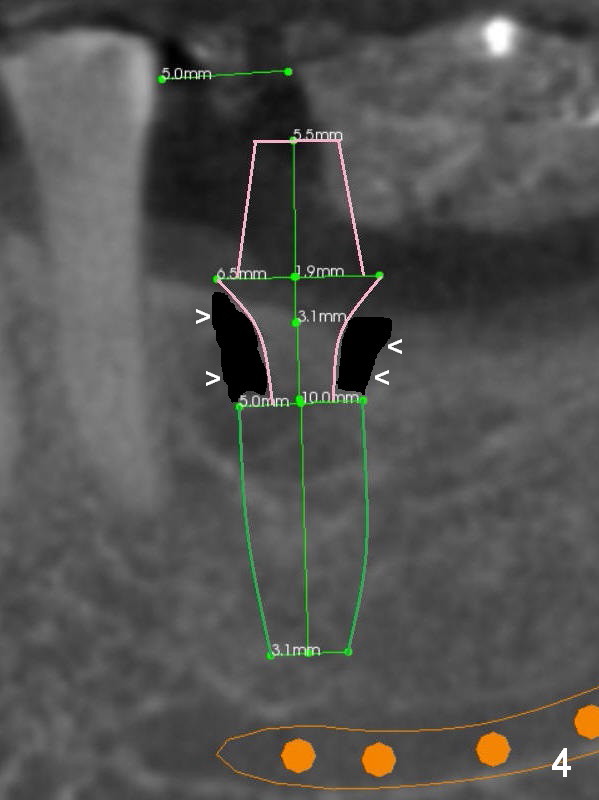

A 56-year-old man decides to have an implant at #19 after those at #13 and 14 (Fig.1 (S: CT stent)). The coronal section shows the pointed ridge (Fig.2 *). For easy implant placement and reduction in thread exposure, the ridge will be trimmed flat (Fig.3 (black area), or more exactly (funnel shaped Fig.4 (arrowheads to accommodate the shape of the cemented abutment (pink)) or concave (Fig.6)). After placing a 5x10 mm UF implant (green), bone graft to be placed (Fig.5,7 red circles) remains in place followed by collagen dressing (Fig.7 yellow lines).

Since the bone density is low (100-400 U), the last drill will be one for a 4.5 mm implant (underprep). To save the autogenous bone, reduce drill speed to 50 RPM when starting using the drill for 3.8 mm implant.